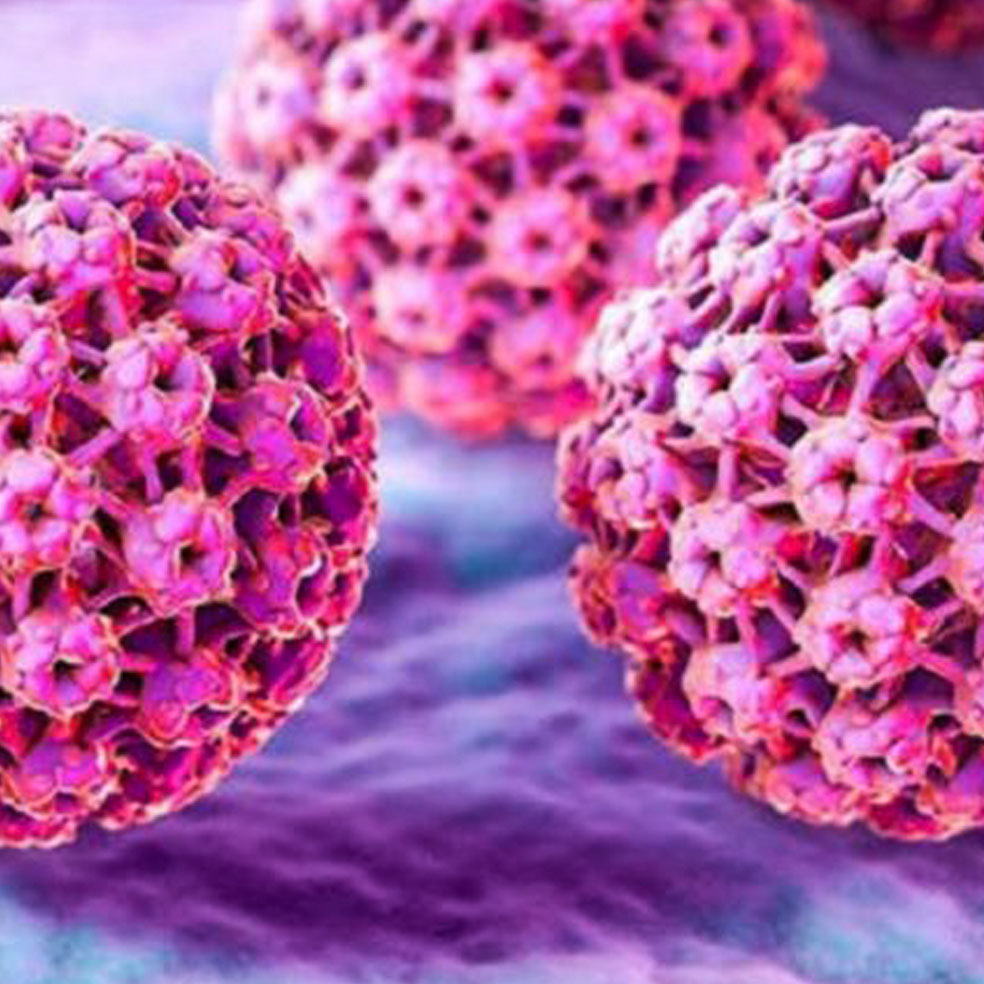

Más de cien tipos del virus del papiloma humano (HPV) se pueden contraer con las relaciones sexuales o el contacto con una piel afectada. Suelen provocar verrugas, manchas blancas y hasta cánceres genitales, y hay personas que no presentan síntomas, pero sí contagian esta infección, que es crónica e incurable.